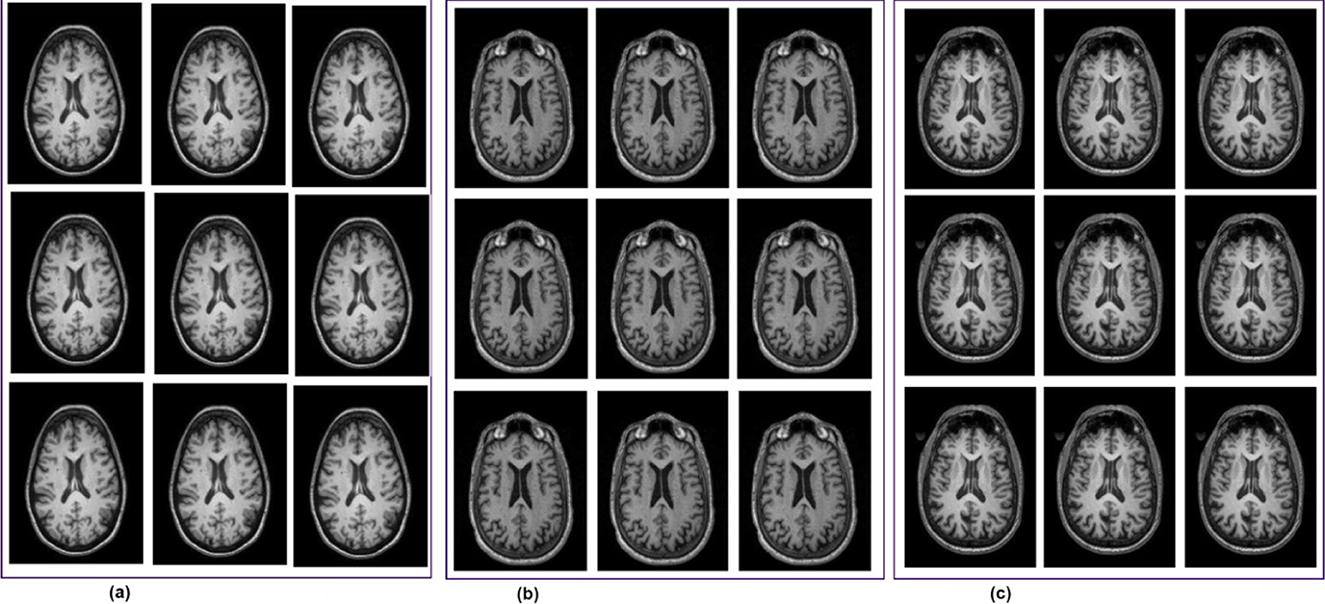

This study utilized the Alzheimer's Disease Neuroimaging Initiative (ADNI) dataset, which by mid-2024 had contributed to over 6,000 peer-reviewed studies worldwide. Over its two decades of operation, ADNI has created more than 47,000 user accounts, with about 26,000 of them currently active, which reflects its global research and ongoing scientific relevance (Alatrany et al., 2024). The ADNI has progressed through several phases to better understand how Alzheimer's disease develops, using brain imaging and data from various groups of people. The first phase, ADNI-1 (2004–2009), gathered baseline data from people with Alzheimer's, healthy individuals, and those with MCI, using scans like DTI, MRI, and PET. ADNI-GO (2009–2011) built on this by focusing on people with early MCI and added functional MRI (fMRI) scans. In ADNI-2 (2011–2016), the study expanded to include more groups, such as late MCI and people with subjective memory complaints, while continuing to collect different types of brain scans to better track Alzheimer's progression. ADNI-3 (2016–2022) kept the same participant groups and scans but improved image quality by using more advanced 3T MRI machines. The latest phase, ADNI-4 (2022 to now), aims to include the underrepresented population through remote cohorts and digital follow-ups. It continues to collect detailed imaging data, enabling researchers to gain deeper insight into Alzheimer's disease across different populations. The ADNI-4 dataset contains three classes: MCI, CN, and AD (Sánchez et al., 2025; Borawar and Kaur, 2023). Representative samples of fMRI scans from the ADNI-4 dataset are represented in Figure 2.

MRI brain scans in three panels labeled (a), (b), and (c). Each panel contains nine axial view images arranged in a three-by-three grid. The scans show variations in brain structures, including clear delineations of the cerebral cortex and ventricles, on a black background.

Figure 2. fMRI scans from the ADNI-4 dataset. (a) Cognitive normal. (b) Mild cognitive impairment. (c) Alzheimer's disease (AD).